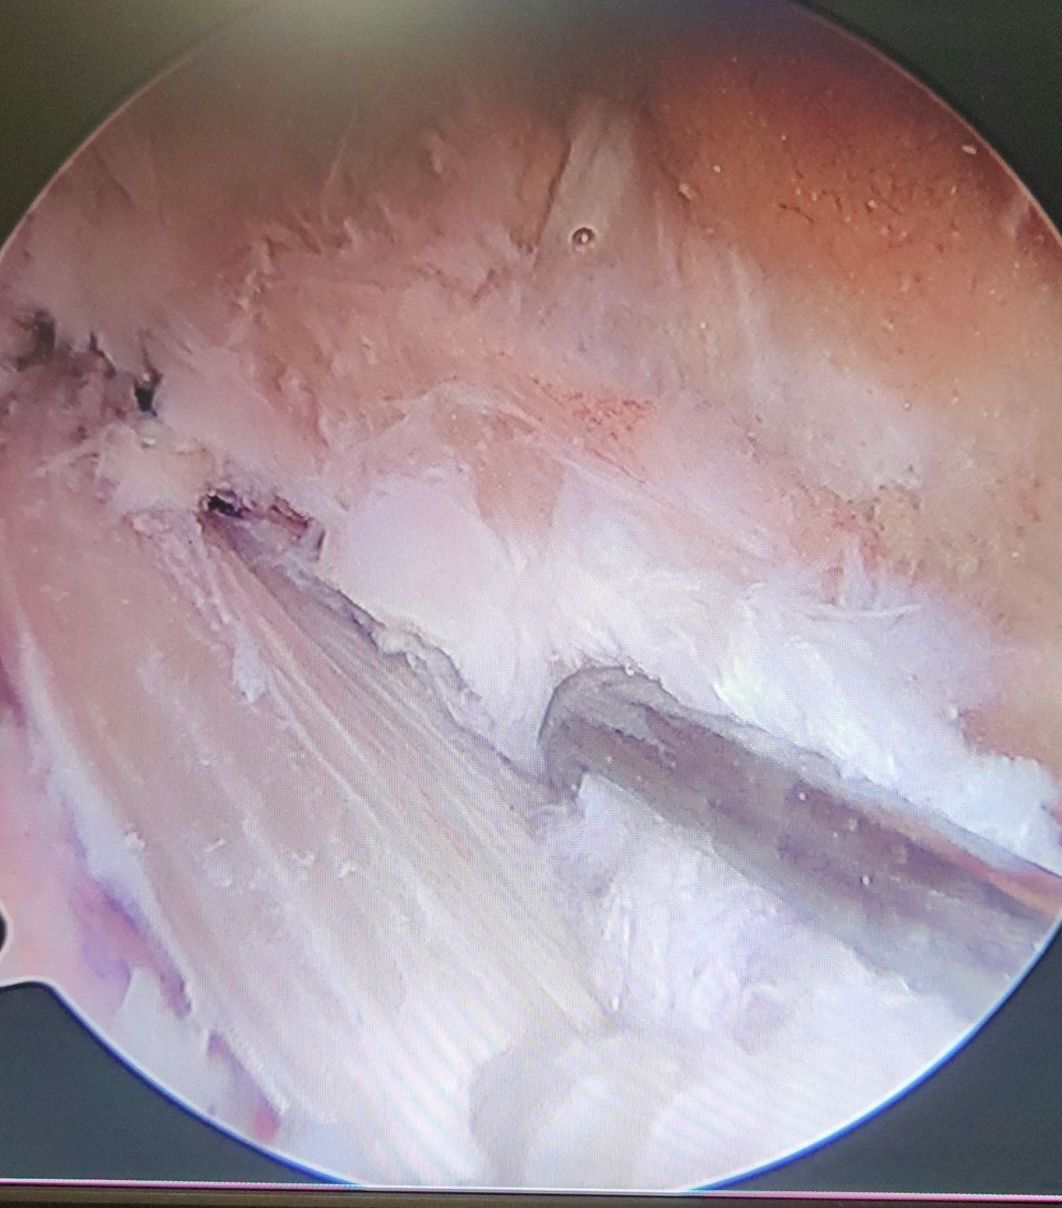

Cirurgia Artroscópica

Patologia Complexa do Joelho